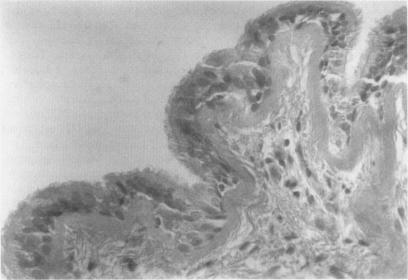

A routine chest radiograph in a 20 year old man revealed a giant air filled cavity of the left hemithorax under tension. At thoracotomy a large left lower lobe intraparenchymal cyst required lobectomy and the pathological findings were consistent with a bronchogenic cyst. Although tension bronchogenic cysts are common in infants, this case demonstrates their unusual presentation in an adult.